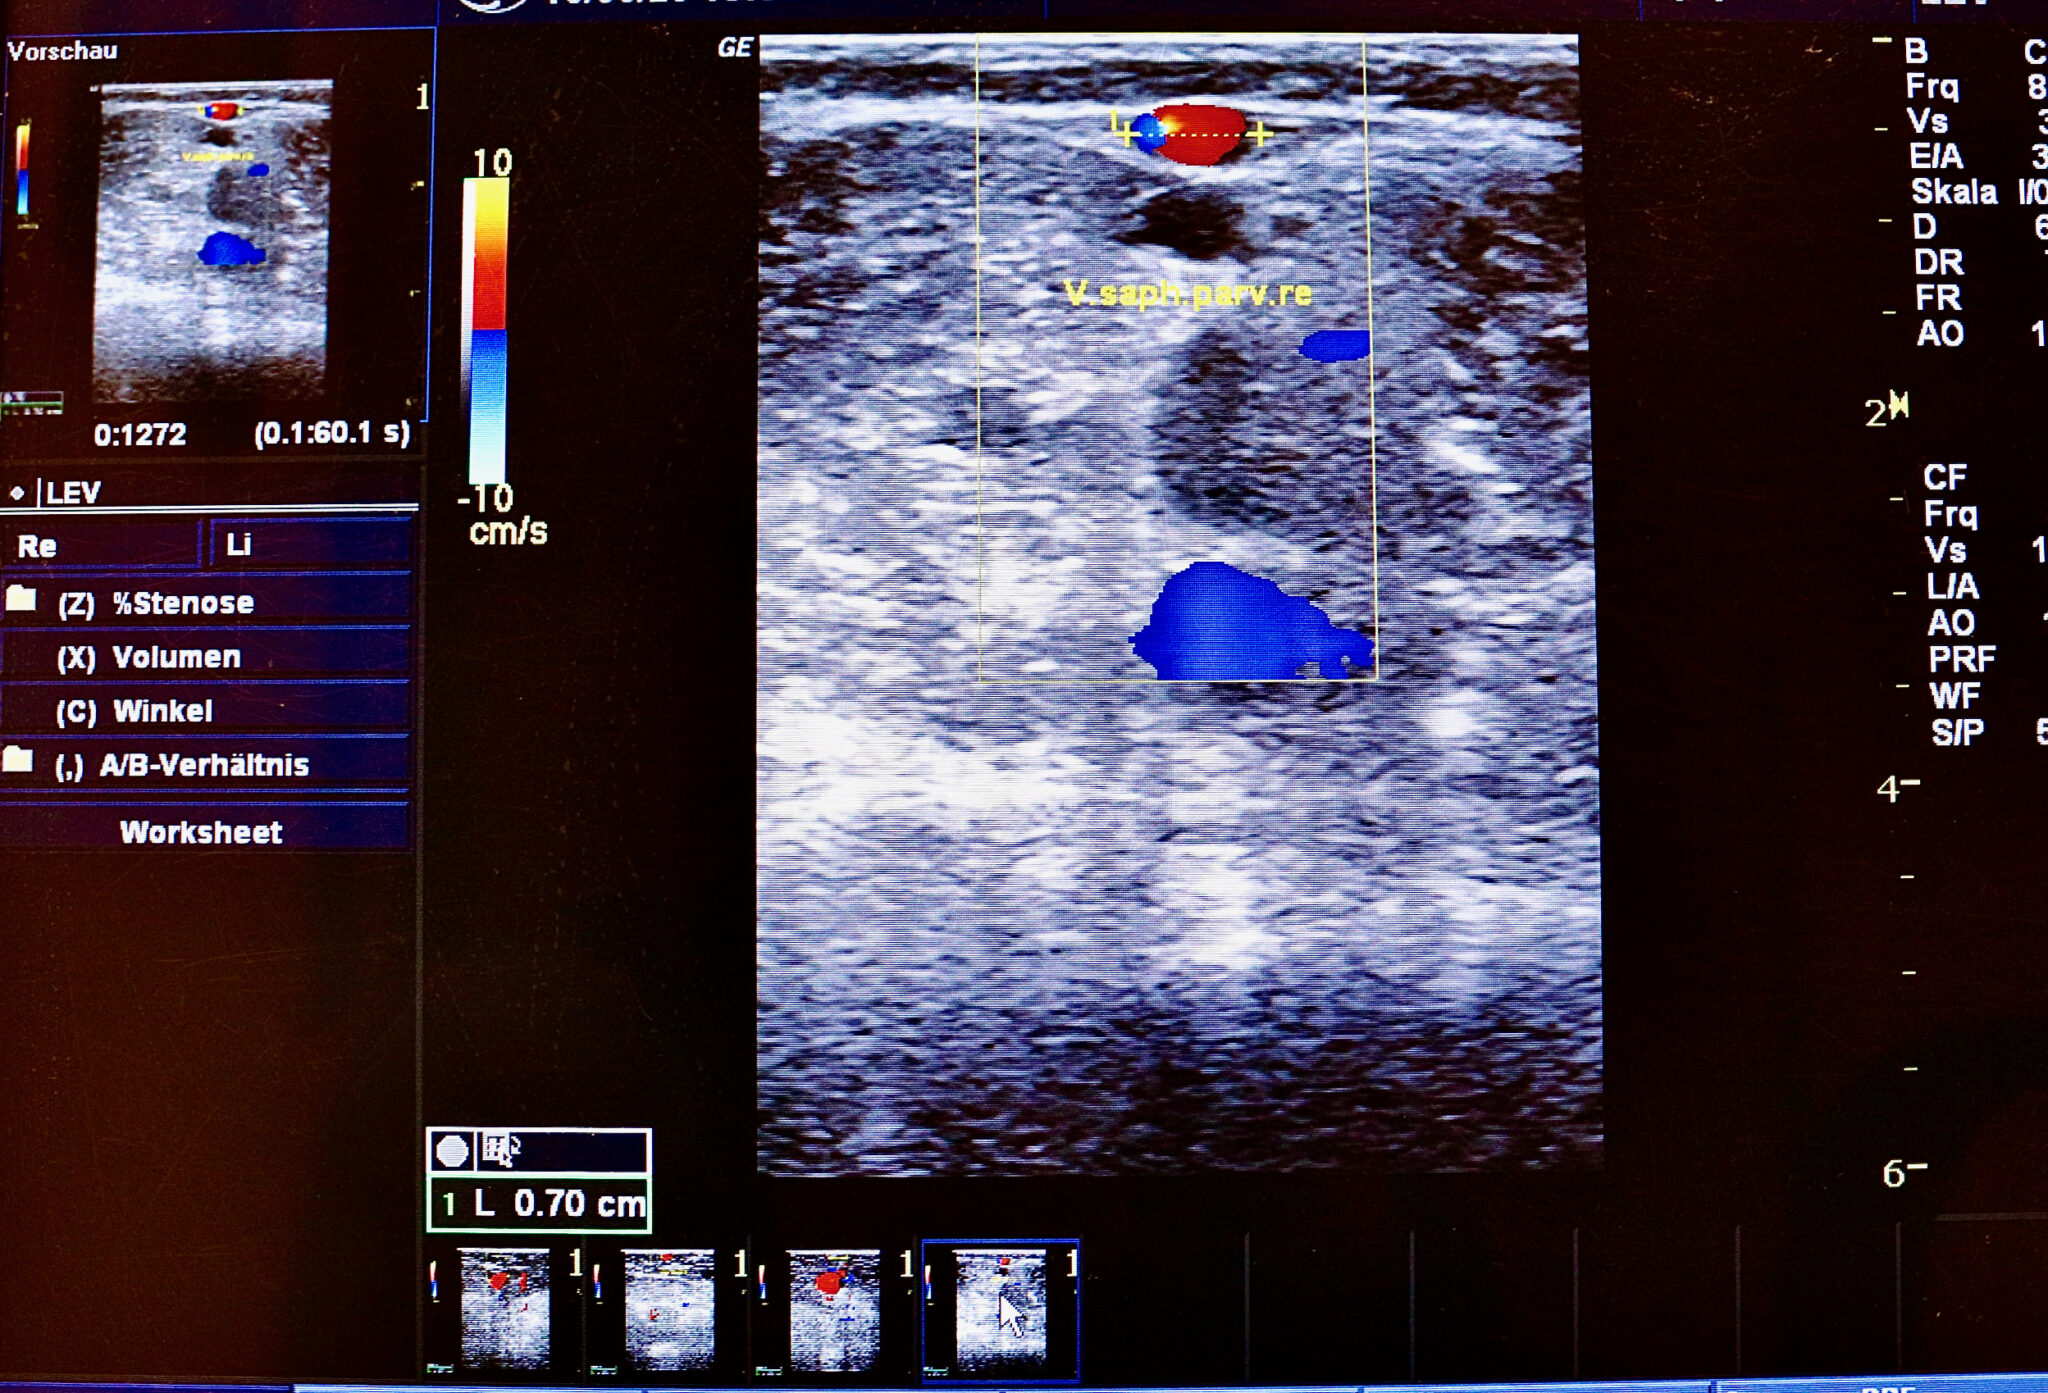

Saphenion®: Therapie bei Beinvenenthrombosen – Mobilisierung und Kompression! Saphenion®: Therapie bei Beinvenenthrombosen – Allein in Deutschland sterben über 40 000 Menschen jedes Jahr an den Folgen einer Lungenembolie – das sind mehr Todesfälle als im Strassenverkehr, bei AIDS, Prostata – und Brustkrebs zusammen! Weltweit steht . Die heute noch eingesetzten chirurgischen Op – Techniken am Venensystem wurde nach dem Zweiten Weltkrieg von Linton (1949), Dodd und Cockett (1956) sowie von May . Die bisher auf dem Markt befindlichen Laser – und Radiofrequenzkatheter .Ich habe den Eid 1988 an der Humboldt Univeristät in Berlin sprechen und ablegen dürfen – mit der sog.Saphenion® Rostock: Friedrich Trendelenburg als Rostocker Chirurg. Behandlungen dieser Art, uneingeschränkt weiterempfehlen. 90%) Frauen betrifft.Saphenion®: Varicose vein therapy in edema – lower leg edema and its causes. Erwartungsgemäß sind und bleiben die 3 mittels Kleben verödeten Stammvenen verschlossen.The Saphenion® fact check vein glue for varicose veins: Results from 141 months of vein glue for varicose veins. Der Autor dieser News war von 1982 – 1988 Student der Humboldt -Universität in Berlin im Fach Medizin und kennt alle im Buch Genannten als Dozenten, Seminarleiter und später als Kollegen persönlich.Saphenion®: Geschichte der Krampfadertherapie – Friedrich Trendelenburg. Alleinige Therapie mit Kompressionsstrumpf nach der Entbindung ist aus unserer Sicht nicht mehr .

Mehr als 5000 . Saphenion®: Therapieanalyse Beinödeme –Diagnostik. Saphenion®: bio glue 63 years in medicine – vein glue as an alternative to laser and radio wave catheters in varicose vein therapy.Saphenion® –Moderne Venentherapie bei Krampfadern – schonend, effektiv, endovenös. Die Säulen der Basisdiagnostik sind Anamnese, Inspektion und Palpation und sollten in dieser Reihenfolge durchgeführt werden.Saphenion®: Biokleber 63 Jahre mediziner Einsatz – Venenkleber als Alternative zu Laser – und Radiowellenkatheter bei der Krampfadertherapie. Saphenion®: Krampfadertherapie beim Ödem – Ödeme sehen wir in unseren Venenpraxen recht häufig.